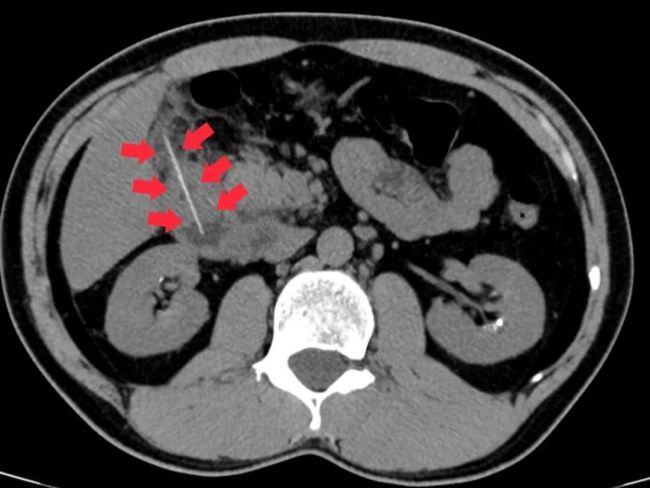

急诊科医生立即为他安排了腹部CT检查,结果显示一根牙签滞留在十二指肠降部,并且尖端已经刺穿肠管壁,引发了局限性腹膜炎。情况危急,如果任由发展可能导致感染扩散甚至休克等严重并发症,危及生命。陈先生随即被收治入院。

外科团队迅速完成术前检查,科主任麦伟锦组织多学科会诊,决定采取“消化内镜优先、手术兜底”的方案。医师李伟杰向陈先生详细解释了治疗思路,消除了他的疑虑。手术中,医师冯锦杭操作电子胃肠镜,清晰定位异物并巧妙调整角度,最终成功将牙签完整取出,并对穿孔处进行了钛夹封闭。整个过程仅用时20分钟,创伤小、恢复快。